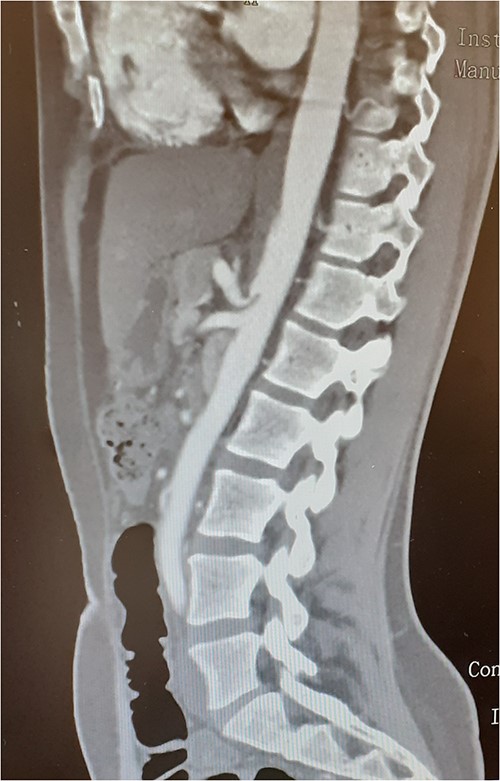

A 37-year-old woman with autoimmune thyroiditis, epilepsy, anti-erythrocyte S antibody and with suspected mixed cryoglobulinemia under study was evaluated for recurrent postprandial abdominal pain with 6 months of evolution, fullness and vomiting with copious meals and weight loss of about 7 kg in 6 months, having already performed a computed tomography angiography (CTA) that revealed MALS (Fig.1). In collaboration with the General Surgery Department, a section of the MAL and lysis of the adhesions by laparoscopic approach was performed. On the third postoperative day, the patient developed a chylous fistula that resolved with conservative strategy including oral diet discontinuation, parenteral nutrition and octreotide. At 1 year follow-up, the patient showed clinical improvement in abdominal pain and food tolerance, and imagiological improvement (Fig.2).

Compression of the celiac artery origin compatible with MALS; note the indentation on the superior wall of the celiac artery, leading to focal stenosis and absence of arterial wall thickening close to the stenosis.